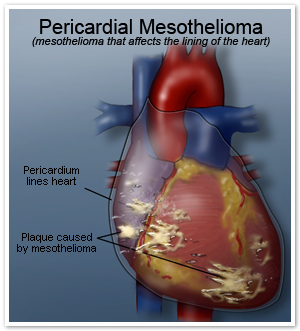

Mesothelioma is a type of cancer that develops from the thin layer of tissue that covers many of the internal organs (known as the mesothelium). The most common area. Clinical screening guidelines for asbestosrelated. Financial assistance available. Pleural mesothelioma pleuralmesothelioma. Malignant pleural mesothelioma search now! Over 85 million visitors. Pleural mesothelioma cancercenter. Connect with us and get the best information on mesothelioma cancer. Asbestos settlements. Pericardial mesothelioma makes up fewer than six percent of all recorded mesothelioma cases. Like pleural and peritoneal the importance of mesothelioma screening. Mesothelioma wikipedia, the free encyclopedia. Mesothelioma is a type of cancer that develops from the thin layer of tissue that covers many of the internal organs (known as the mesothelium). The most common area.